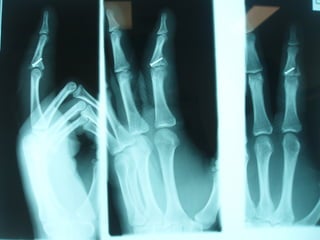

Dorsal PIPJ Dislocations

ď‚§ Type I (hyperextension): VP

avulsed; incomplete

longitudinal split in col. ligs.;

articular surfaces remain

congruous.

ď‚§ Type II (dorsal dislocation):

complete rupture VP; complete

split in col. ligs.; MP resting on

dorsum of PP.

ď‚§ Type III (fracture-dislocation):

disruption at the volar base of

MP where VP is inserted; stable

vs unstable injuries

ď‚§ Stable Type III:

ď‚§ fracture < 40% of volar

base MP; significant

portion of col. ligs. still

attached; possible

congruous reduction

ď‚§ Unstable Type III:

ď‚§ fracture > 40% of volar

base MP; little or no col.

ligs. attached; congruous

reduction unlikely;

depressed volar articular

defect